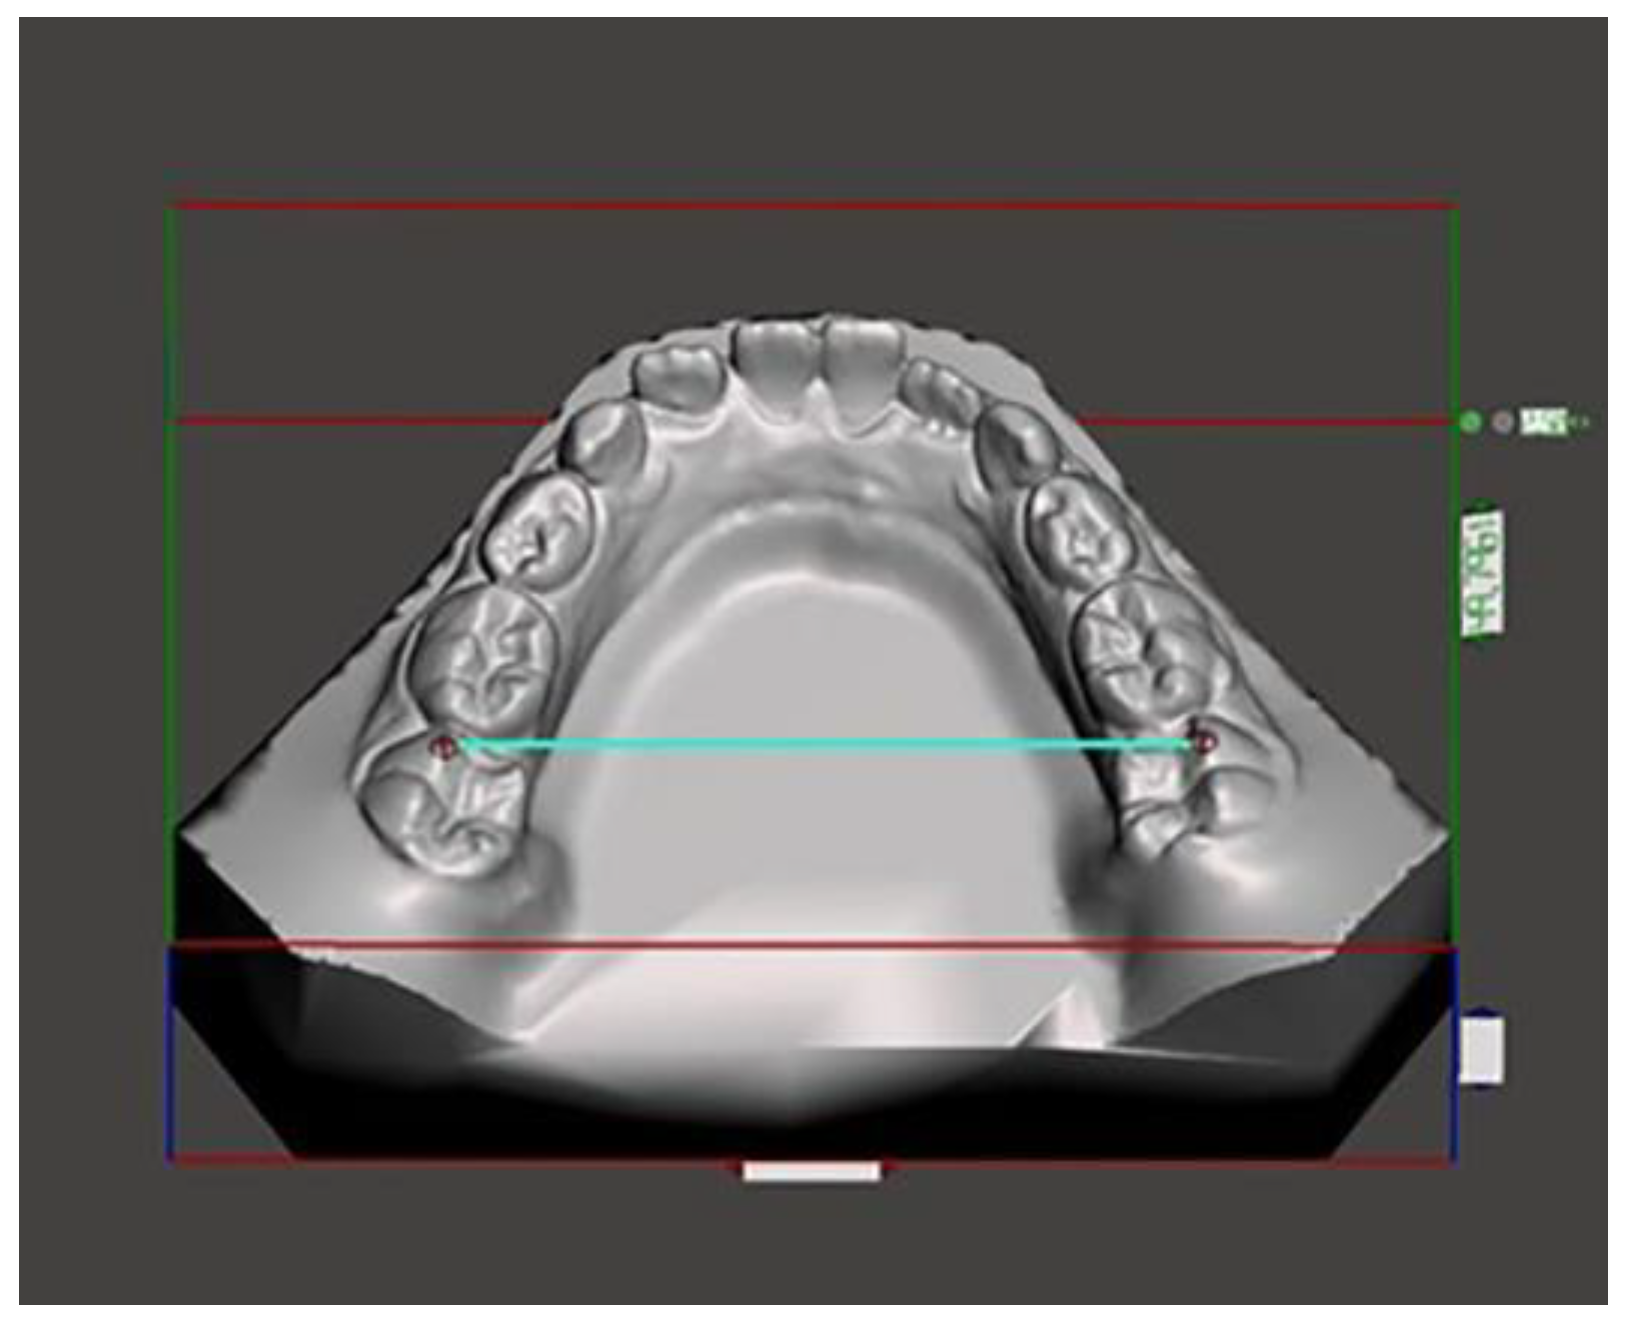

Figure 4.

Posterior mandibular width measured on the disto-vestibular cusp of the first molar.